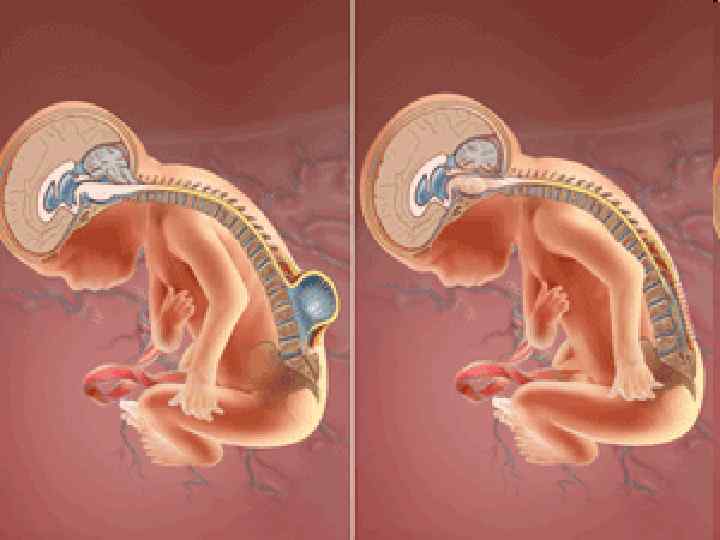

120

121